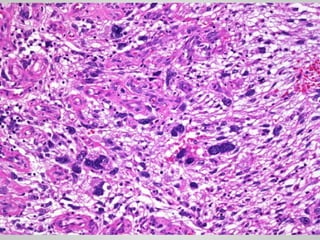

Palmar Fibromatosis (Dupuytren contracture)

• Gray-white, firm, poorly demarcated

masses

• Varying from 1 to 15 cm in greatest

diameter

• Rubbery and tough

• Marked infiltration of surrounding

muscle, nerve and fat.

• Cytologically bland fibroblasts

arranged in broad sweeping fascicles

amid dense collagen

• Gray-white, firm,poorly demarcated masses • Varying from 1 to 15 cm in greatest diameter • Rubbery and tough • Marked infiltration of surrounding muscle, nerve and fat. • Cytologically bland fibroblasts arranged in broad sweeping fascicles amid dense collagen